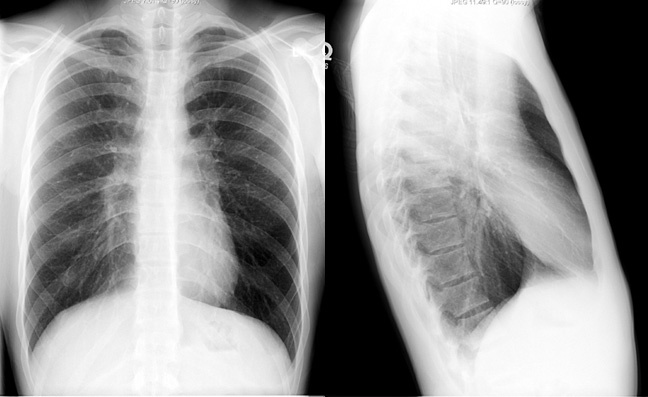

1. X-ray

폐기종에 의해서 폐실질이 변화되어 방사선 투과성이 증가하여 정상인에 비해 흉부가 전체적으로 검게 보인다. 다만, X선 사진이 검은 것은 촬영조건에 따라 상당히 달라지기 때문에 주의를 요한다.

1-1. 폐의 과팽창

경한 폐기종에서는 찾기 힘들고 중등도나 심한 경우에 나타난다.

횡격막이 낮아지고 평편해진다. 측면 사진에서 흉곽의 전후경이 증가하여 술통(barrel chest) 같은 모양이 되고 흉골후방공간(retrosternal space)이 비정상적으로 넓어지고 길어지며 흉골이 전방으로 휜다.

1-2. 폐혈관의 변화

폐기종이 심해지면 말초 혈관의 수와 크기가 현저히 감소하고 중심혈관의 크기가 커진다. 폐동맥고혈압(pulmonary arterial hypertension)이 동반된다.

1-3. 심장의 변화

폐의 과팽창이 심해지면서 심장의 횡경이 작아지고 좀 더 중심부에 놓여진다. 폐성심(cor pulmonale)이 발생하면 우심실 확대소견이 나타난다.

1-4. 국소기포(bulla)나 소기포(bleb)

기포는 미만성 폐기종에 흔히 동반되며 주로 폐야의 변연부에 나타난다. 폐의 방사선 과투과로 X-ray로 찾기 어려울 수 있다.